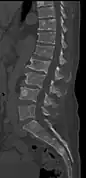

The diagnostic examination of a person with suspected multiple myeloma typically includes a skeletal survey. This is a series of X-rays of the skull, axial skeleton, and proximal long bones. Myeloma activity sometimes appears as "lytic lesions" (with local disappearance of normal bone due to resorption) or as "punched-out lesions" on the skull X-ray ("raindrop skull"). Lesions may also be sclerotic, which is seen as radiodense.[76] Overall, the radiodensity of myeloma is between −30 and 120 Hounsfield units (HU).[77] Magnetic resonance imaging is more sensitive than simple X-rays in the detection of lytic lesions, and may supersede a skeletal survey, especially when vertebral disease is suspected. Occasionally, a CT scan is performed to measure the size of soft-tissue plasmacytomas. Nuclear Medicine Bone scans are typically not of any additional value in the workup of people with myeloma (no new bone formation; lytic lesions not well visualized on nuclear bone scan).

CT scan of the lower vertebral column in a man with multiple myeloma, showing multiple osteoblastic lesions: These are more radiodense (brighter in this image) than the surrounding cancellous bone, in contrast to osteolytic lesions, which are less radiodense.